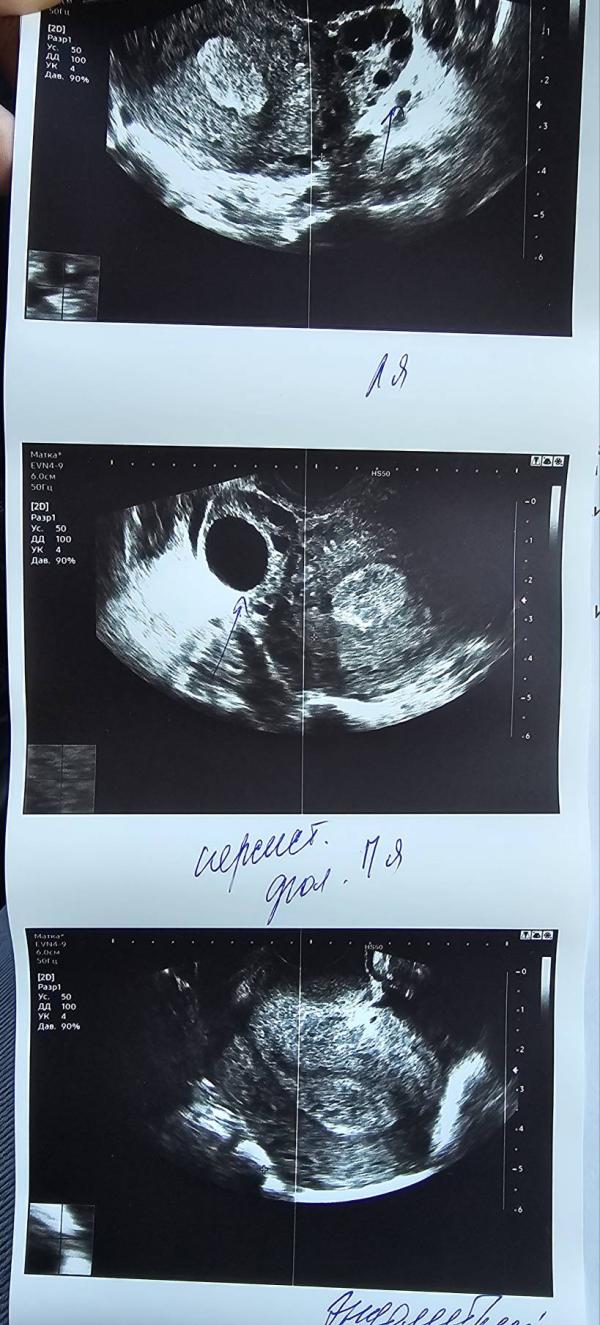

Девочки, всё прекращаю делать тесты, сходила я все таки на узи, как я изначально и предполагала овуляции не было ну уже и не будет в этом цикле. Жду КД

Вообще не понимаю почему левый яичник тянуло , если в правом доминантный фолликул